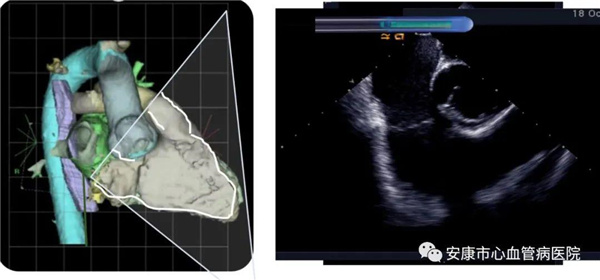

心律失常團(tuán)隊(duì)在11月6日為患者在ICE引導(dǎo)下行房撲射頻消融術(shù)。穿刺左鎖骨下靜脈,導(dǎo)絲走行證實(shí)了合并永存左上腔靜脈。穿刺右股靜脈,分別送入心腔內(nèi)超聲導(dǎo)管和消融電極,超聲下建立右心室、右心房、左心室、左心房、二尖瓣和三尖瓣及三尖瓣峽部模型。ICE就像術(shù)者多了一雙天眼,可以對心臟內(nèi)部結(jié)構(gòu)一目了然,360度無死角觀察心臟結(jié)構(gòu),可以做到“所視即所及”。建模后,消融三尖部峽部,房撲很快終止,轉(zhuǎn)為竇性心律,手術(shù)獲得成功!手術(shù)用時(shí)僅70分鐘,術(shù)后病情穩(wěn)定,安全返回病房。

心腔內(nèi)超聲(Intracardiac Echocaiography ICE)是將微型的換能器安裝在心導(dǎo)管的尖端,再經(jīng)外周血管(動脈或靜脈)送至心腔,換能器發(fā)射聲波,然后將接受到的回波經(jīng)計(jì)算機(jī)處理后形成超聲圖像。由于換能器放置在心腔內(nèi),不受空氣等因素的干擾,因此比經(jīng)食道超聲檢查圖像更加清晰,可以辨別心內(nèi)的細(xì)微結(jié)構(gòu),臨床上主要用于指導(dǎo)心律失常的射頻消融治療。